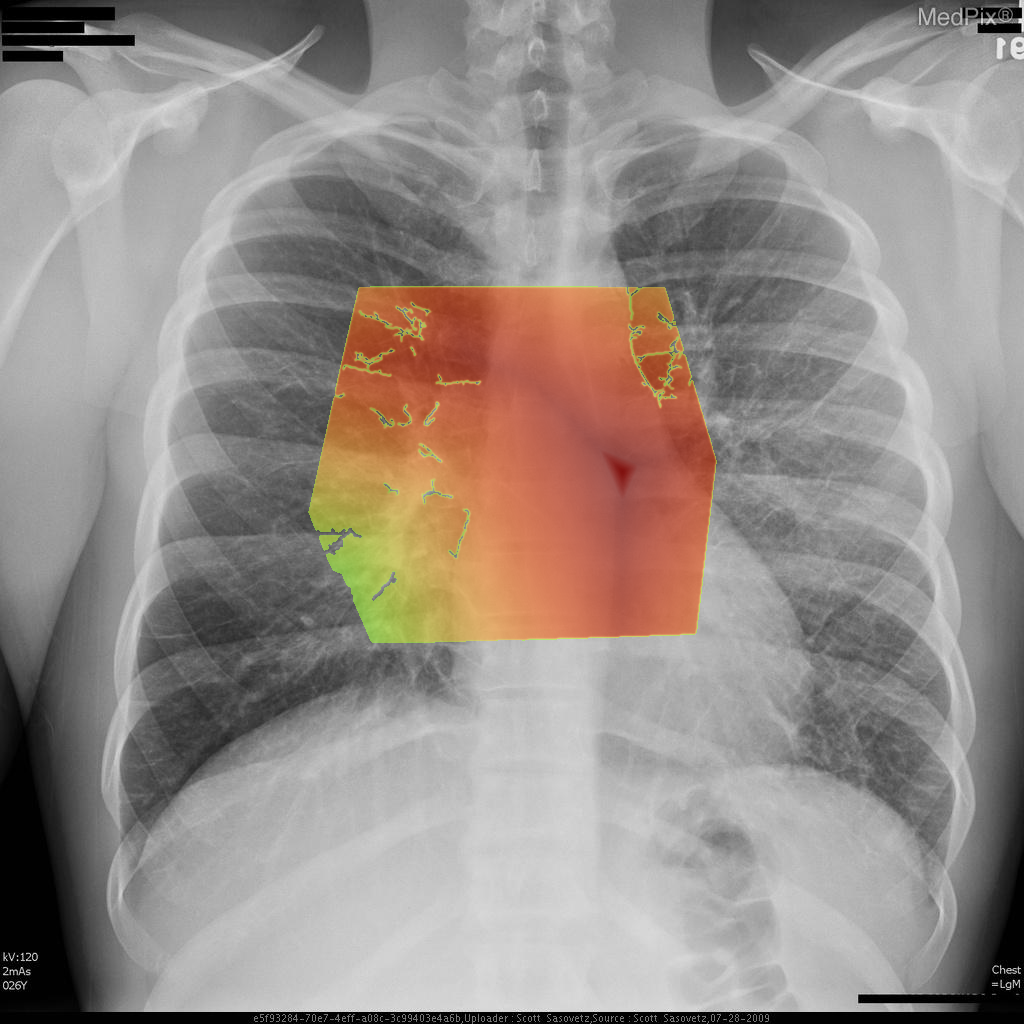

- Adequate inspiratory chest X-ray with clear visualization of both lungs, mediastinum, and diaphragm.

- Cardiac silhouette is normal in size; cardiac apex lies image-right (patient-left), consistent with expected anatomy.

- Pulmonary vasculature appears mildly prominent centrally, with increased perihilar markings suggestive of vascular congestion.

- Subtle hazy ground-glass type opacities noted in the perihilar regions, extending outward in a symmetric pattern (more conspicuous centrally than at the periphery).

- No focal lobar consolidation, no pleural effusion, and no pneumothorax identified.

- Costophrenic angles appear sharp bilaterally.

- Bony thorax visualized without acute abnormality.

Findings are most consistent with pulmonary edema. The hazy bilateral perihilar opacities and vascular congestion suggest an interstitial/alveolar fluid process consistent with pulmonary edema rather than focal pneumonia or chronic interstitial disease. The absence of cardiomegaly makes non-cardiogenic causes more likely (such as swimming-induced pulmonary edema). Context consistency: Consistent — the described clinical context (young swimmer with acute onset) aligns well with non-cardiogenic pulmonary edema findings. Confidence: 80%.